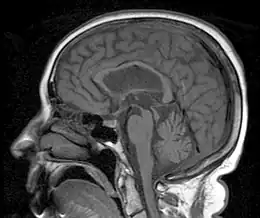

In PSP the midbrain (red) to pons area (blue) ratio is typically reduced to 0.12[3]

Person with progressive dementia, ataxia, and incontinence. A clinical diagnosis of normal-pressure hydrocephalus was entertained. Imaging did not support this, however, and on formal testing, abnormal nystagmus and eye movements were detected. A sagittal MRI image shows atrophy of the midbrain, with preservation of the volume of the pons. This appearance has been called the "hummingbird sign" or "penguin sign". Also, atrophy of the tectum is seen, particularly the superior colliculi. These findings suggest the diagnosis of progressive supranuclear palsy.[31]

MRI is often done to diagnose PSP. MRI may show atrophy in the midbrain with preservation of the pons giving a "hummingbird" sign appearance and Mickey Mouse sign.[32]